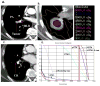

Materials and methods: We delivered SBRT to 27 patients, 13 with Stage I and 14 with isolated recurrent NSCLC. A central/superior location was defined as being within 2 cm of the bronchial tree, major vessels, esophagus, heart, trachea, pericardium, brachial plexus, or vertebral body, but 1 cm away from the spinal canal. All patients underwent four-dimensional computed tomography-based planning, and daily computed tomography-on-rail guided SBRT. The prescribed dose of 40 Gy (n = 7) to the planning target volume was escalated to 50 Gy (n = 20) in 4 consecutive days.

Results: With a median follow-up of 17 months (range, 6-40 months), the crude local control at the treated site was 100% using 50 Gy. However, 3 of 7 patients had local recurrences when treated using 40 Gy. Of the patients with Stage I disease, 1 (7.7%) and 2 (15.4%) developed mediastinal lymph node metastasis and distant metastases, respectively. Of the patients with recurrent disease, 3 (21.4%) and 5 (35.7%) developed mediastinal lymph node metastasis and distant metastasis, respectively. Four patients (28.6%) with recurrent disease but none with Stage I disease developed Grade 2 pneumonitis. Three patients (11.1%) developed Grade 2-3 dermatitis and chest wall pain. One patient developed brachial plexus neuropathy. No esophagitis was noted in any patient.